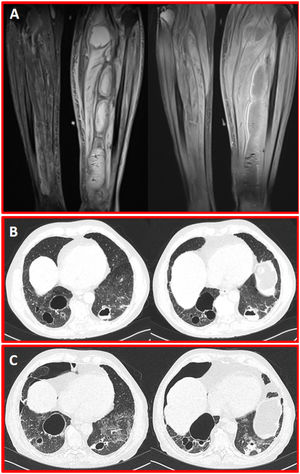

A 74-year-old man with membranous glomerulonephritis was admitted to our hospital with left calf pain and swelling. The patient had no immunosuppressive treatment. His body temperature was 39.5°C, and blood pressure was 75/55mmHg. Laboratory tests revealed the following: white blood cell count, 23,000cells/mm3; hemoglobin, 14.7g/dL; platelet count, 127,000cells/mm3; creatinine, 1.13mg/dL; C-reactive protein, 97mg/dL; and D-dimer, >35μg/mL. Echocardiography showed no presence of heart valves’ vegetations. To examine calf inflammation, magnetic resonance imaging (MRI) was performed. The MRI showed formation of giant intramuscular abscesses in the posterior side of the left cruris (Fig. 1A). Percutaneous drainage was performed for the calf abscess. The cultures of blood and abscess content revealed the presence of methicillin-resistant Staphylococcus aureus. Intravenous vancomycin was administered as the antibiotic treatment. That patient began showing productive cough with purulent sputum. Chest computed tomography (CT) showed different images of septic pulmonary embolism in both lungs (Fig. 1B). Shortness of breath appeared five days after the commencement of the treatment. The control CT scan revealed the right pneumothorax (Fig. 1C). The pneumothorax resolved spontaneously within ten days.

(A) Coronal proton density and postcontrast T1-weighted MR images show giant intramuscular abscesses in the posterior of the left cruris. (B) Axial CT scans in parenchyma window show multiple cavitary septic embolisms in both lungs. (C) Control CT scans five days after from the presentation scan reveal the right pneumothorax secondary to septic embolism.